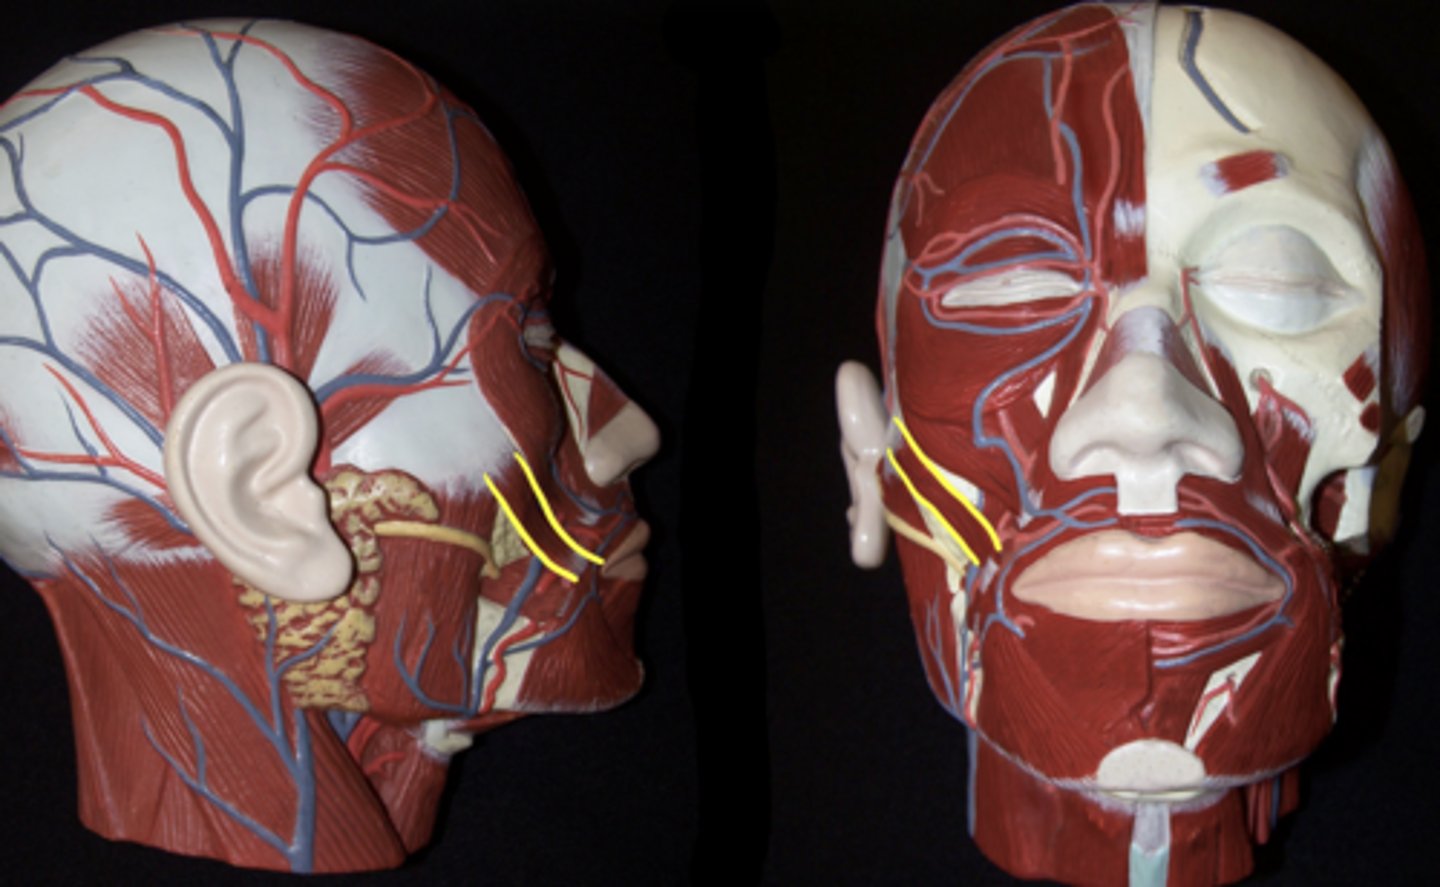

Temporalis

Masseter

Sternocleidomastoid